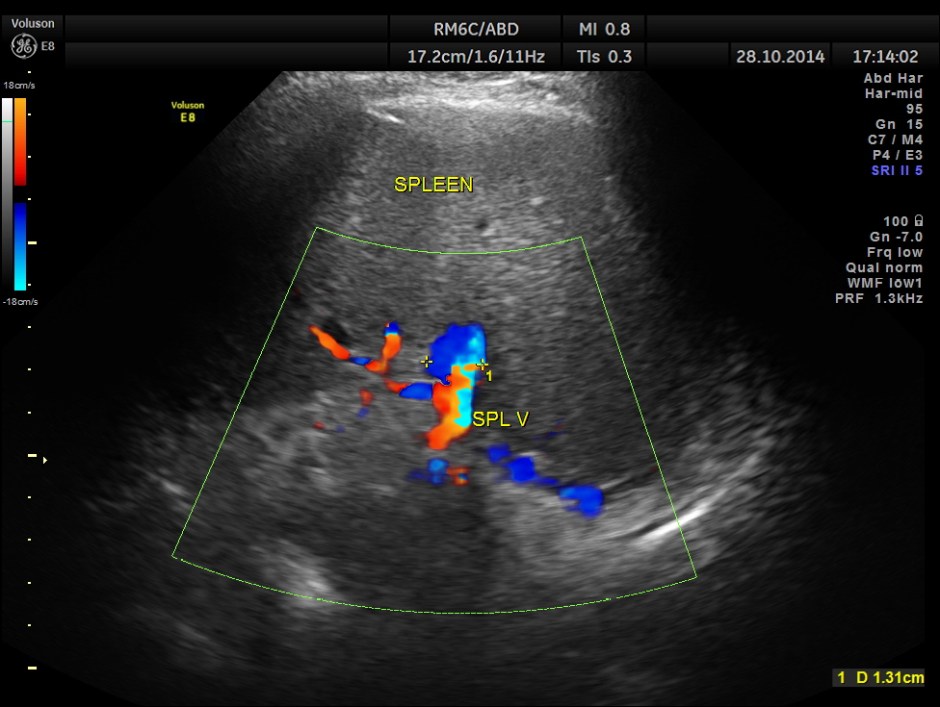

Mild splenomegaly with mildly dilated splenic vein is seen.

Epigastric varices are also seen.